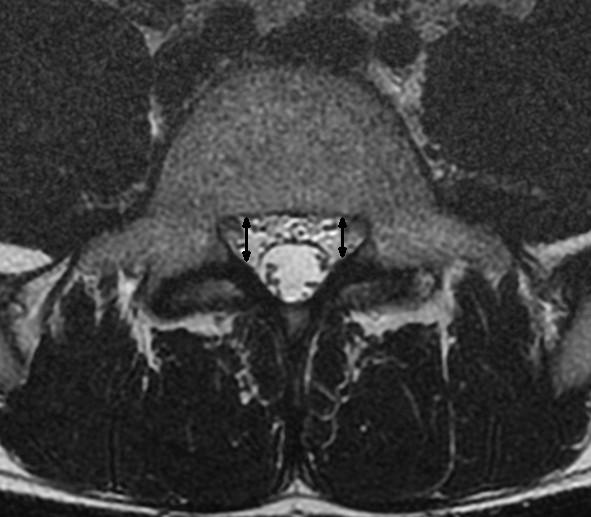

25 studies reporting on radiological signs of LSS and four systematic reviews related to the evaluation of different treatments were found. Ten different parameters were identified to quantify lumbar spinal stenosis. Most often reported measures for central stenosis were antero-posterior diameter (< 10 mm) and cross-sectional area (< 70 mm(2)) of spinal canal. For lateral stenosis height and depth of the lateral recess, and for foraminal stenosis the foraminal diameter were typically used. Only four of 63 primary studies included in the systematic reviews reported on quantitative measures for defining inclusion criteria of patients in prognostic studies.

发现 25 篇报告 LSS 影像学征象的研究和 4 篇与评估不同治疗方法相关的系统评价。确定了 10 个不同的参数来量化腰椎椎管狭窄症。最常报道的中央狭窄测量值为椎管前后径(<10mm)和横截面积(<70mm²)。对于侧方狭窄,通常使用侧隐窝的高度和深度以及椎间孔狭窄的椎间孔直径。在纳入系统评价的 63 项主要研究中,仅有 4 项报告了用于确定预后研究患者纳入标准的定量测量值。